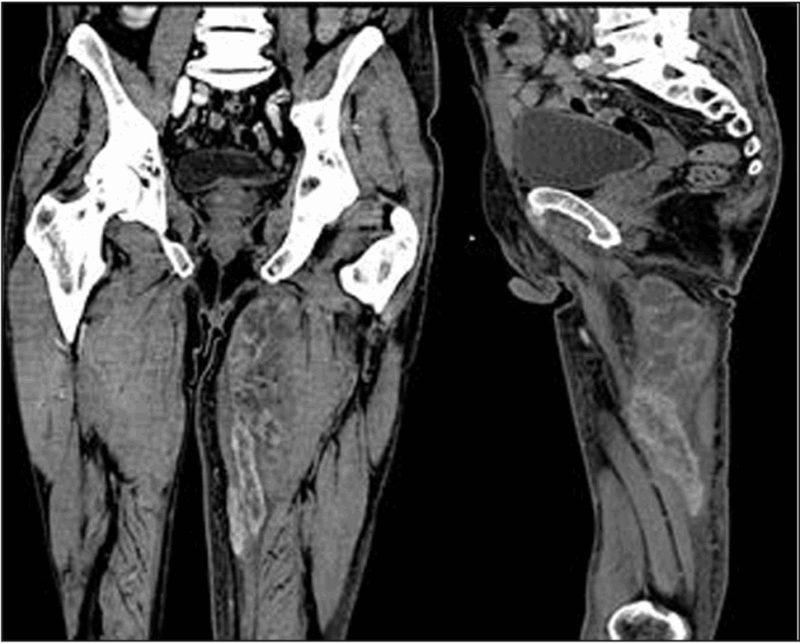

MRIを待っている間, 昨日多発肺転移が見つかった大腿骨頚部骨折の超高齢患者さんの造影CTの結果を確認しました. お腹の中の腫瘤にも造影効果が認められたので, 大腸癌の疑いが強まりました. 外科の先生に見ていただいたところ, 診断を確定するには生検が必要と言われました. 今後, 家族と相談して, さらに検査するかどうかを決める予定としました.